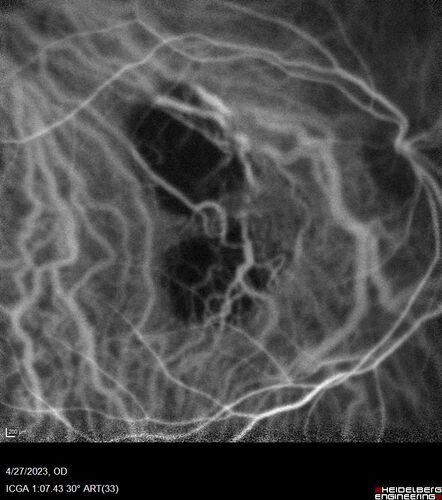

73 year old female Diagnosed with POHS in the past and treated with laser in the right eye in 1994 with vision loss.  She moved from Tampa to Largo in 2017 and started seeing Dr. Cohen.  She had her last injection in the left eye 2015 prior to moving to Largo.  She has been treated intermittently in the left eye and has been resistant to Anti-VEGF injections.  Her vision is good in the left eye. Images are from April 2023 one month following a Vabysmo injection in the left eye.

VA 20/200 OD, 20/25 OS